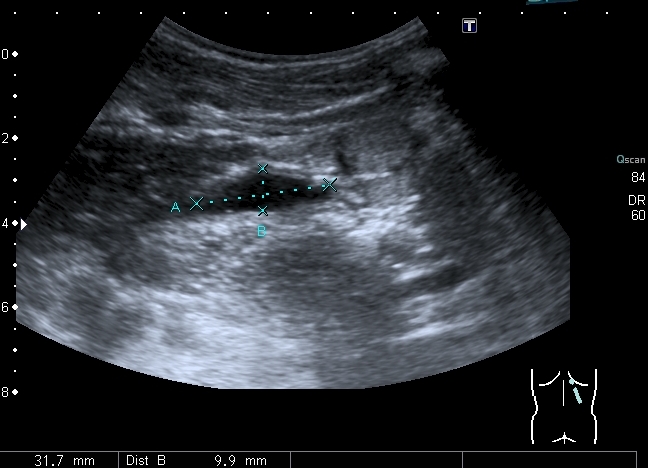

Определяется небольшое расширение лоханок обеих почек, стенки их гиперэхогенные, утолщены.

I20121224144608984.jpg

Меня больше всего заинтересовало тканевое образование в нижнем полюсе левой почки - гиперэхогенное, многоузловое. Есть мысли про причину такого состояния почек, но пока хочу выслушать мнения коллег. Буду очень благодарен за отзывы.

Спленомегалии нет. печень без признаков фиброза . Почки уменьшены ( правая - 50 х 20 мм, левая - чуть больше , но за счёт образования нижнего полюса). В левой почке в образовании - есть одиночная небольшая киста ( см клип про почки №3), но на поликистоз непохоже. Ещё одно "но" : с аутосомно - рецессивной поликистозной болезнью почек до 10 лет не живут.

Еще раз пересмотрел клипы. У меня есть впечатление, что подрасширены ЧЛС почек - так ли это? - на этом факте основывается предположение о возможной рефлюкс-нефропатии. Если такого впечатления нет,то нужно вернуться к варианту АРПКБ почек. Что касается продолжительности жизни у больных с АРПКБ почек, то все зависит от того сколько процентов клубочков поражено и насколько поражена печень.